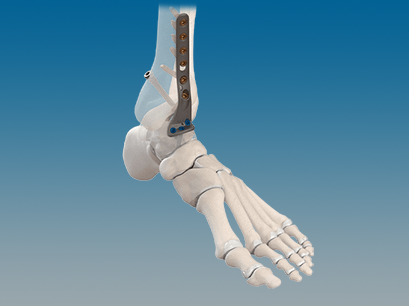

CONMED Foot and Ankle offers tailored innovation and simplified solutions. Explore our complete portfolio of arthroplasty, biologic, fixation, implant, suture anchor, and instrumentation offerings for foot and ankle surgery.

QUANTUM® Total Ankle System with OrthoPlanify™ Patient Specific Instrumentation